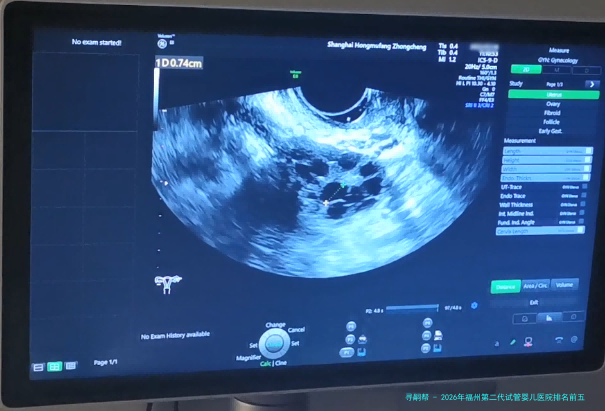

2026年福州第二代试管婴儿医院排名前五公立三甲实力对比:附费用与详细解读

2026年福州第二代试管婴儿医院排行前五公立三甲力量相比:附费用与详细解读